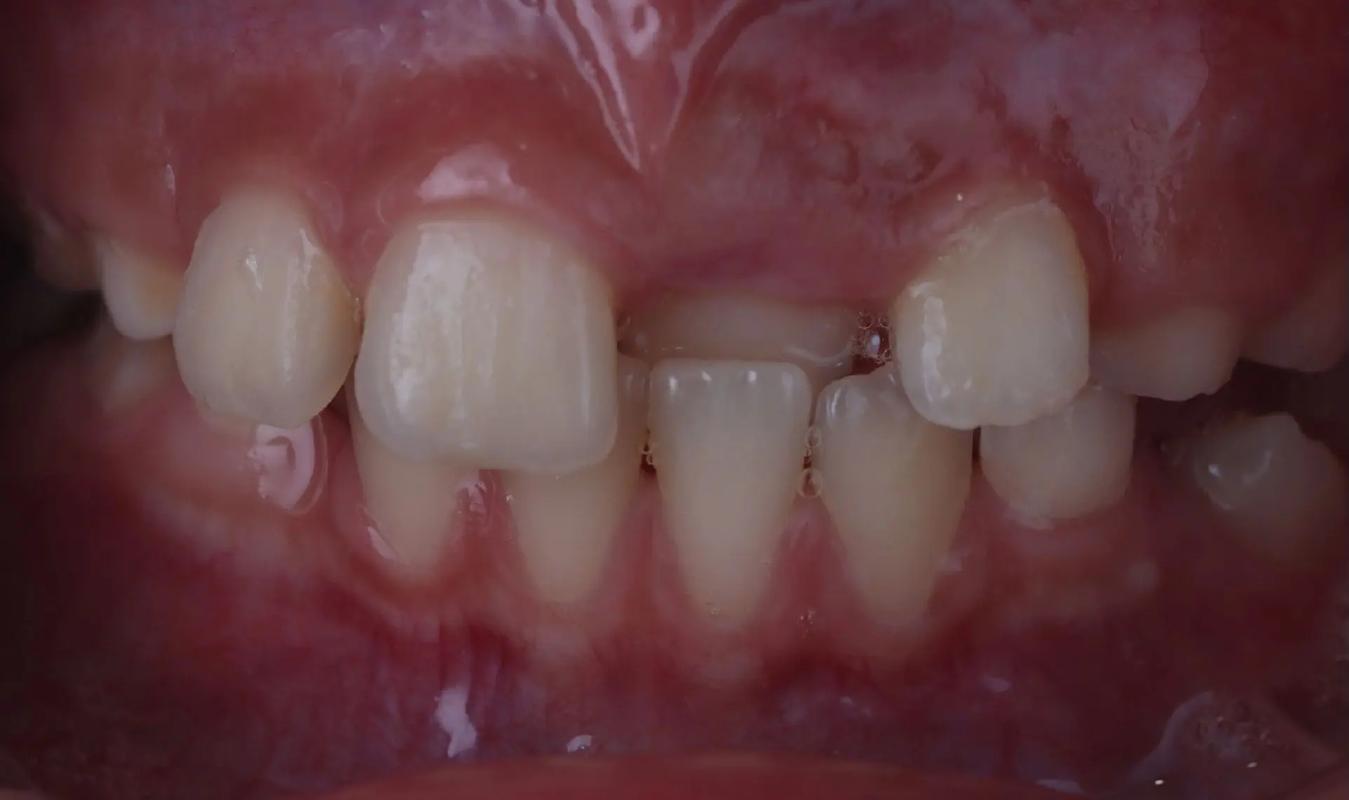

面相牙齒反合 牙齒反頜的圖片

牙齒反合,俗稱“地包天”,是指下頜骨相對于上頜骨前突,下排牙齒咬合在上前排牙齒前方,形成一種“倒咬合”的外觀。這種面相特征不僅影響美觀,還潛藏著潛在的健康隱患。